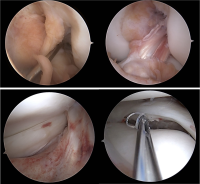

Cartilage restoration

Meniscus surgery

Arthroscopic meniscal repair - (5-50)